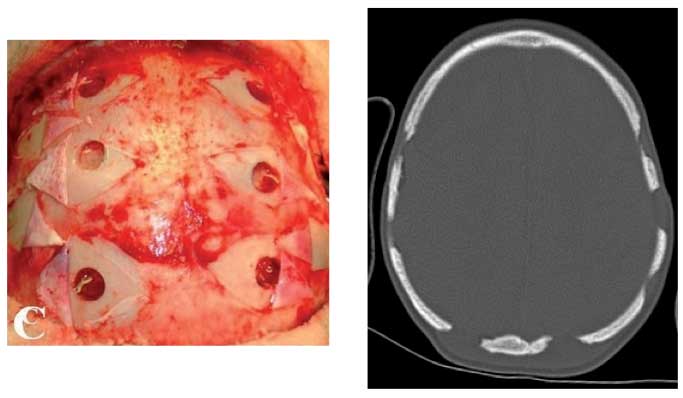

Il bambino � stato quindi inviato presso un centro specialistico per eseguire un intervento di rivascolarizzazione corticale indiretta: l�encefalosinangiosi mette a contatto il parenchima cerebrale con i vasi durali attraverso fori multipli praticati nelle ossa craniche (Figura 4).

Figura 4. Ricascolarizzazione diretta o indiretta